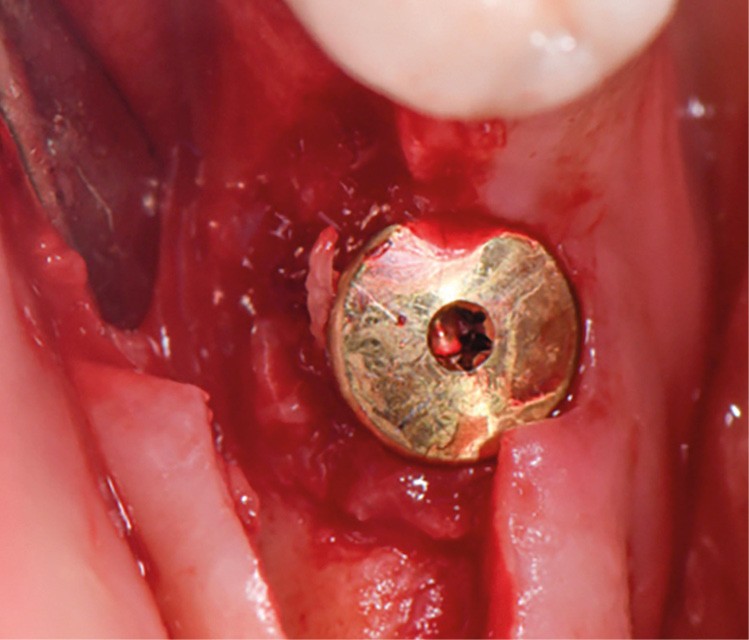

Actes préopératoires

La couronne a été déposée et une vis de couverture mise en place. La patiente a reçu un nettoyage supra-gingival général avec une attention particulière pour l’implant 47, et une irrigation locale avec du gel de chlorhexidine et du peroxyde d’hydrogène pour réduire l’inflammation des tissus. De l’amoxicilline (3 x 500 mg) a été prescrite, à commencer la veille de l’intervention chirurgicale.